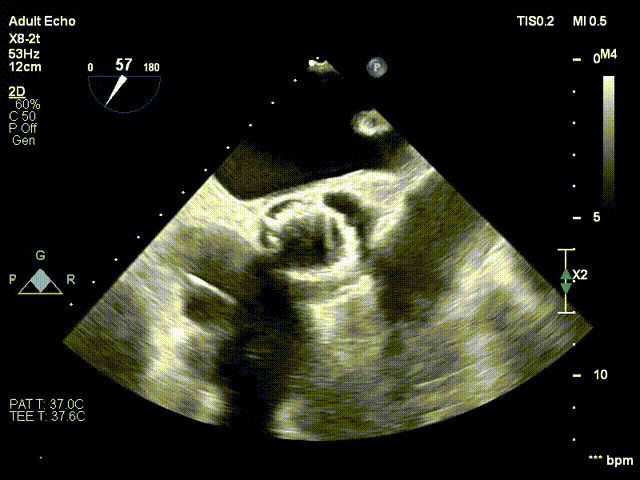

患者病史 男性,74y, 因 “发现心脏瓣膜病 1 年,加重伴喘气半年” 入院。门诊检查显示主动脉瓣重度AS并伴轻-中度AR。患者基础疾病较多:胸腹主动脉多发穿透性溃疡、心功能III级等,手术指征明确,但风险极高。 术前CT LVOT- Annulus 倒梯形,对植入瓣膜有挤压位移风险,Annulus直径23.7mm,瓣叶增厚,钙化集中在无冠窦边缘。 左冠脉开口高度可,瓣叶不长、窦部空间较大,无冠脉风险;室间隔膜部较短,有一定PPI风险,心脏角度37.9°;心室较小,有一定循环崩溃风险,术前注意补液。 术前造影角度及入路:血管入路散在钙化、无迂曲;主动脉弓条件好、双侧股动脉直径大、右股穿刺点侧壁存在环形钙化 左右重合位:RAO 7° CAU 21° 右窦中心位:LAO2 1° CAU 1° 手术策略 20mm球囊预扩后植入AV26瓣膜,同时做好预防循环崩溃、传导阻滞的应急预案。 术中挑战 1)球囊预扩:20mm球囊预扩时无明显 “腰征”,但存在少量反流,提示瓣膜钙化与解剖结构对扩张的阻力不均 2)首次释放偏差:第一次定位释放时,瓣膜在 “开花” 过程中下滑约 3mm,工作位观察显示小弯侧瓣周漏较多(深度超过完全覆膜区),需二次调整。 3)二次精准定位:以猪尾导管为参照,将定位点调整至 “猪尾 - 2mm” 处,结合真实窦底深度(较深)重新释放,最终瓣膜位置稳定,瓣周漏显著减少。 术后即刻效果: 瓣膜形态良好,跨瓣压差从术前的 67mmHg 降至 6mmHg,且无明显瓣周漏,冠脉开口通畅; Commisural Alignment 术后即刻超声: Prostyle A®预装干瓣——助力临床最优化解决方案: √ 平衡的径向支撑力:特殊的解剖结构下位置形态良好,术后跨瓣压差大幅降低,血流动力学改善明显; √ 80%可回收设计:支持术中二次调整释放位置,保证精准释放; √ 平衡的收腰设计&Commissural Alignment设计: 为患者后期冠脉PCI保留了生命通道;